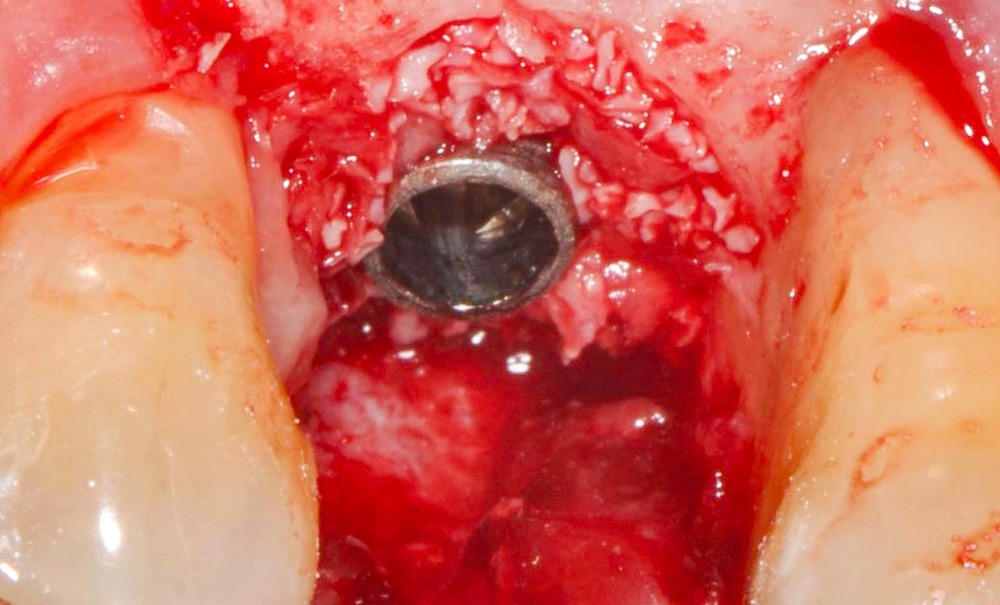

Chez cette patiente, le traitement de la péri-implantite a été réalisé à l’aide d’une technique de régénération osseuse guidée péri-implantaire, dont l’indication a été principalement motivée par la morphologie du défaut osseux. Au-delà de la maîtrise du geste chirurgical, le bon résultat obtenu à trois ans est intimement lié à sa coopération en termes de suivi et de contrôle de plaque.